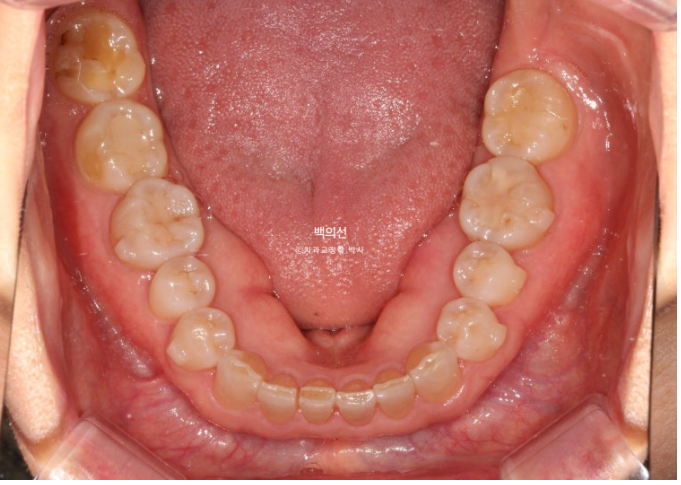

25.02

아래 앞니는 누구나 나이가 들면서 점점 틀어집니다.

앞니를 잡는 뼈가 약해지기도 하고, 평행에 걸쳐 교합력이 어금니들을 앞으로 밀어내는 방향으로 작용하기 때문입니다.

아직 많이 안 틀어졌을 때 배열을 한 번 잡아주는 것이 좋습니다.

아래 앞니 배열은 벌써 가지런해졌습니다.